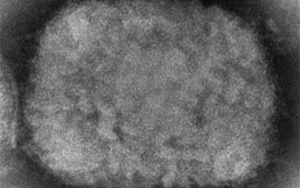

波士頓大學(xué)的研究人員發(fā)現(xiàn)了抑制猴痘病毒復(fù)制的化合物!

來自波士頓大學(xué)喬巴尼安和阿維迪森醫(yī)學(xué)院的研究人員開發(fā)了一種新型化合物,很快就可以用于預(yù)防所有經(jīng)測試的引起人類疾病的痘病毒。